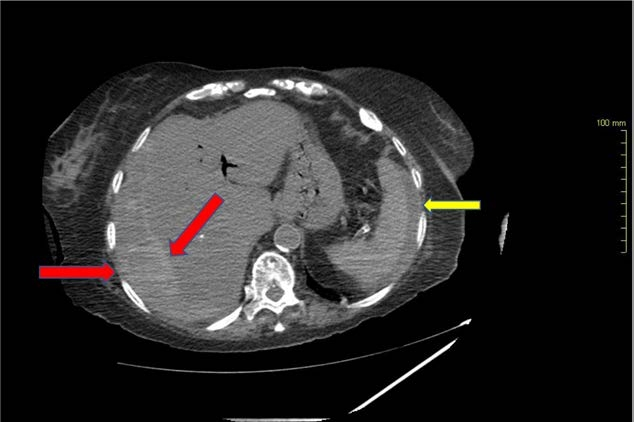

图2 腹部CT轴位图示累及肝右叶的肝包膜下血肿(红色箭头),最大厚度约 37 mm,脾周积液(黄色箭头)提示腹腔积液